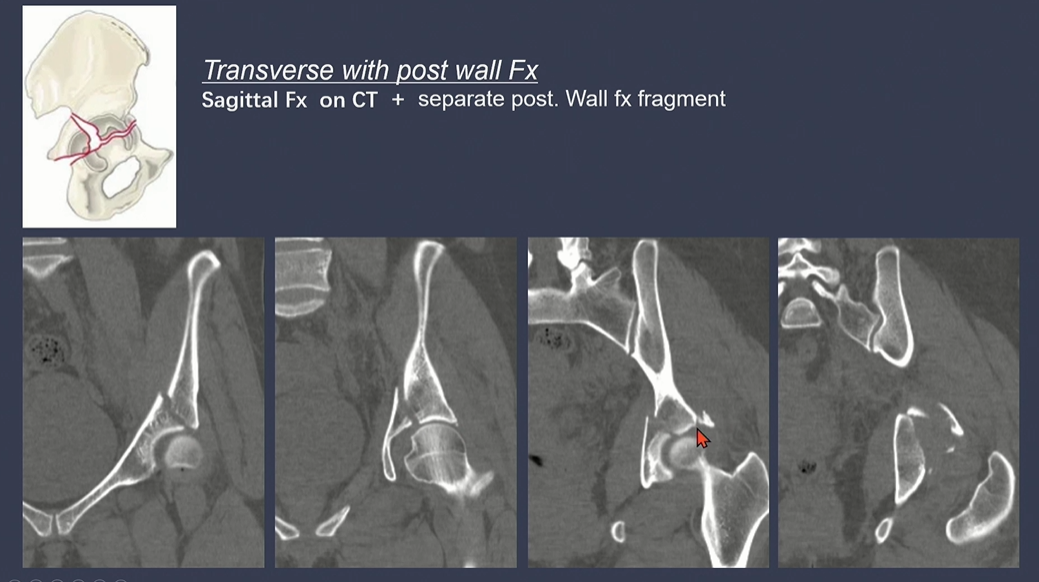

Transverse fracture는 Sigittal로 골절선이 위치 (bone을 위/아래로 나누는 선)

노란색 화살표: anterior column + 녹색 화살표 posterior hemitransverse